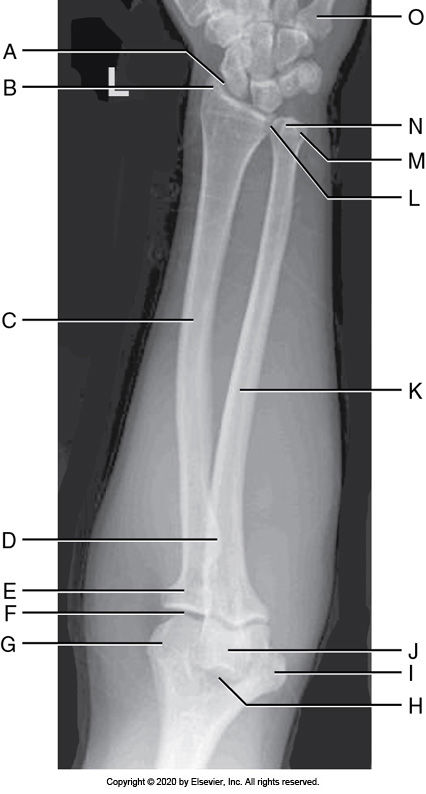

Identify the labeled "K" anatomy in the image below:

Medial epicondyle

Identify the labeled "H" anatomy inn the image below:

Capitulum